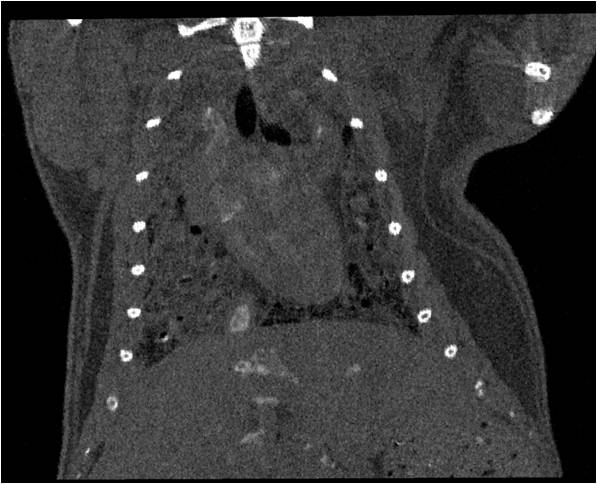

腫瘤血管生成

肺轉(zhuǎn)移

小鼠模式,22.5μm像素

正常

8天 14天

無造影劑注入 造影劑注入